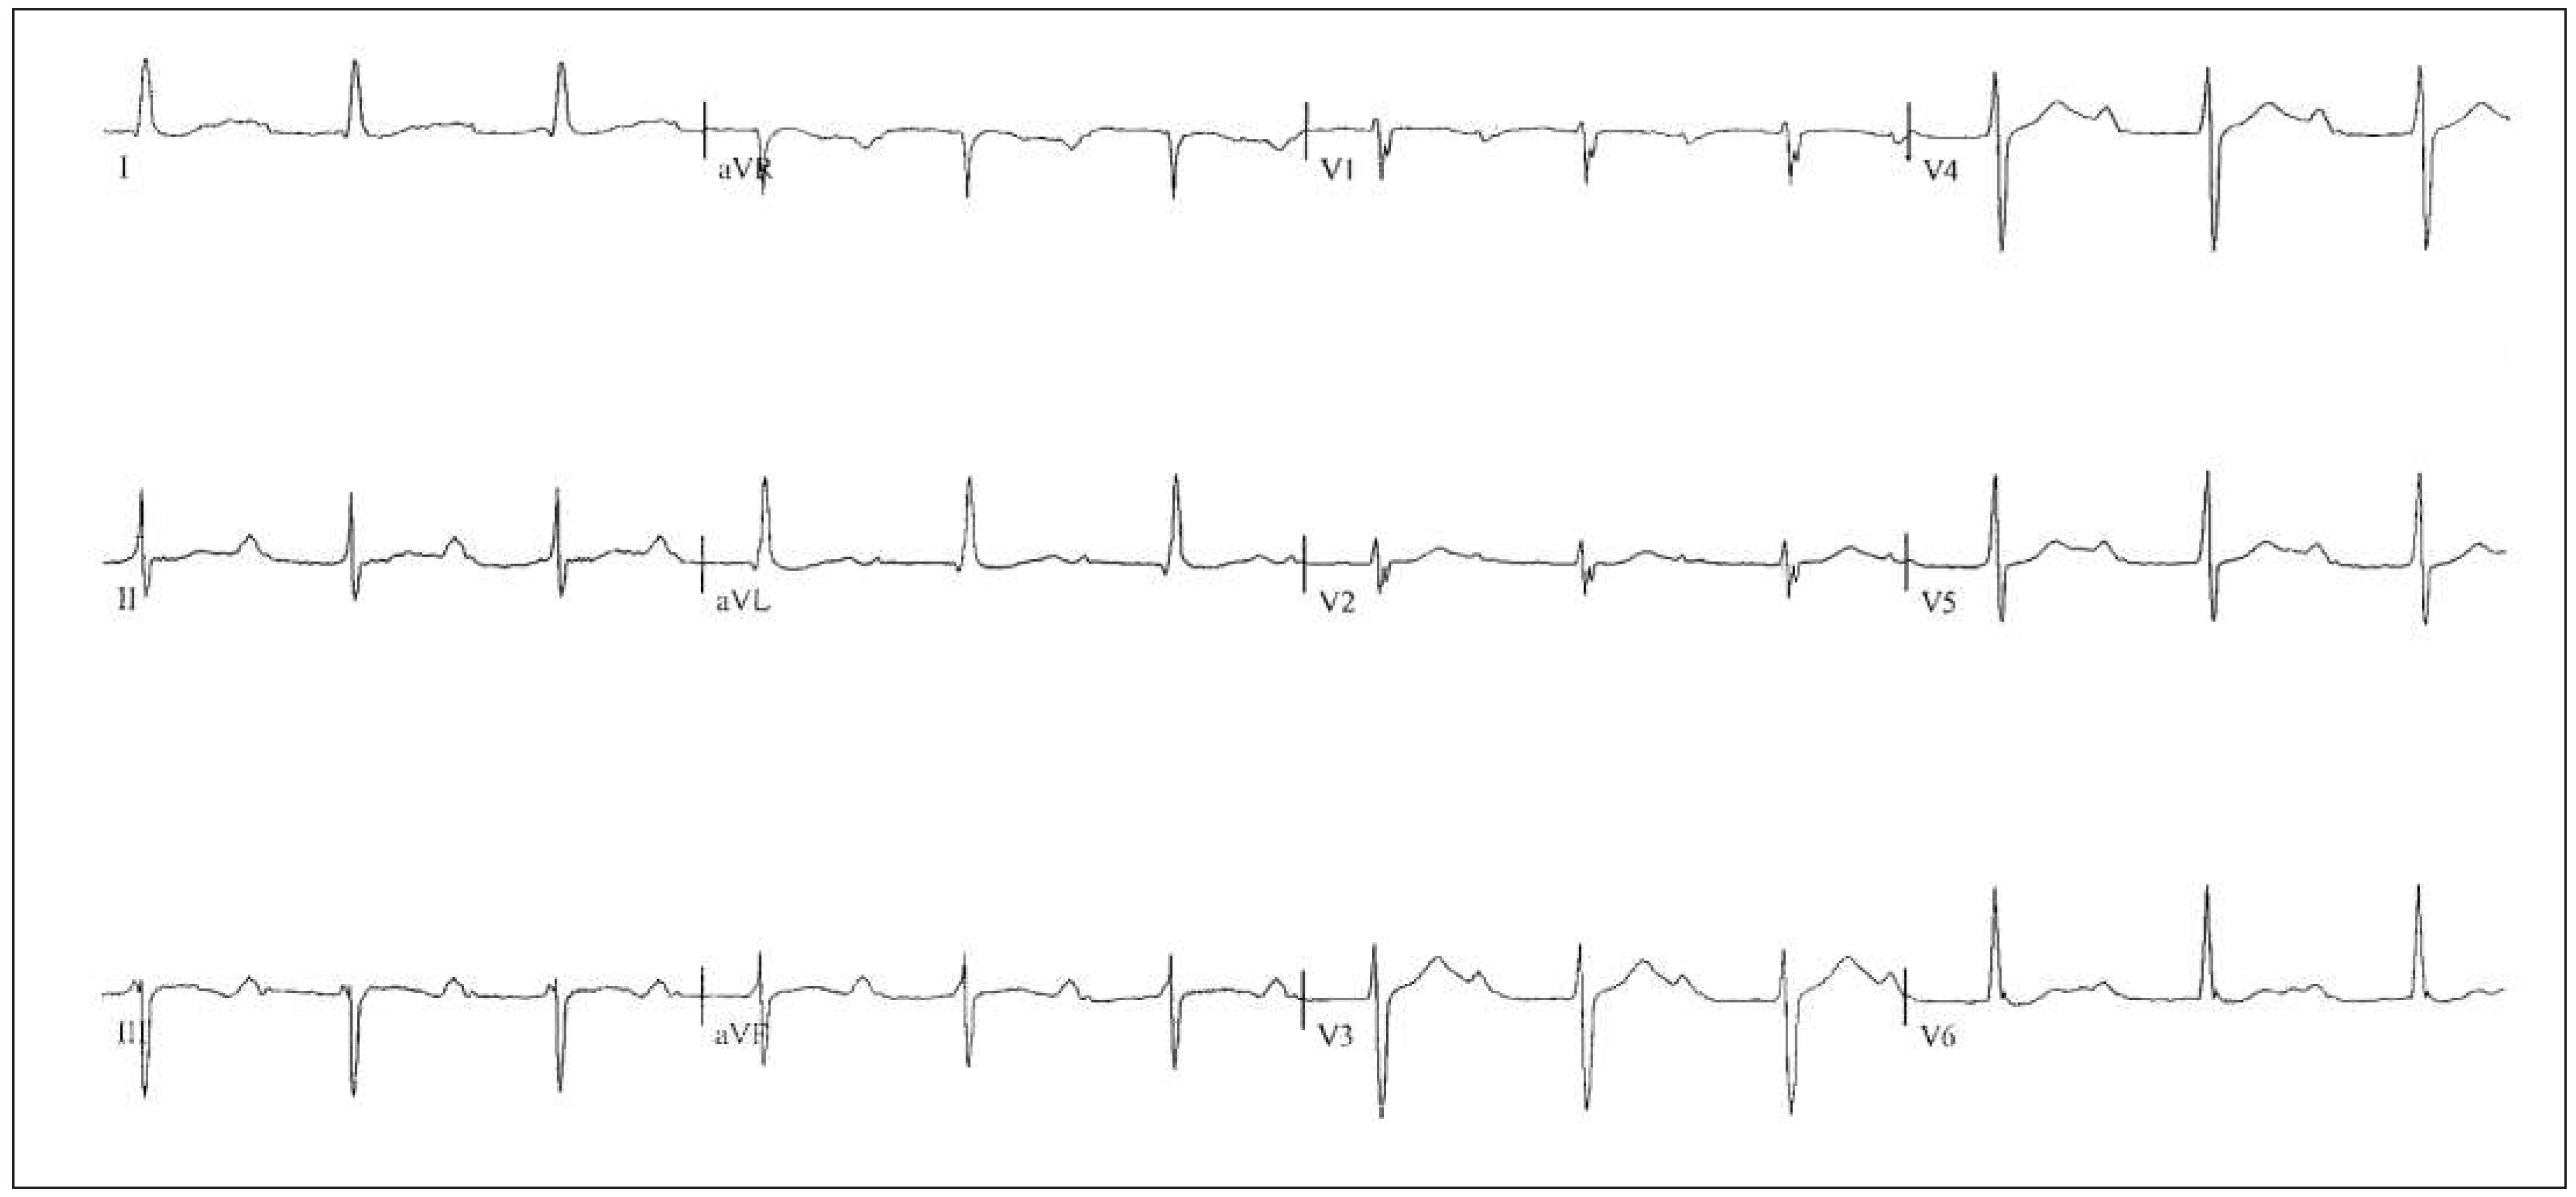

Patient

Six-month follow-up

Sixteen-month follow-up